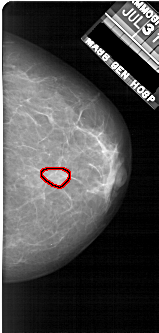

FILE: A_1922_1.RIGHT_CC.OVERLAY

TOTAL_ABNORMALITIES 1

ABNORMALITY 1

LESION_TYPE MASS SHAPE OVAL MARGINS OBSCURED

ASSESSMENT 3

SUBTLETY 4

PATHOLOGY BENIGN

TOTAL_OUTLINES 1

BOUNDARY